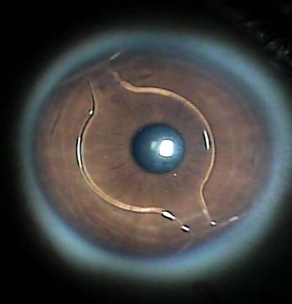

• Colocación de Lentes Fáquicos para Alta Miopía

(Acrysoft Fáquico Cachet) – Usado para la corrección de miopías moderadas a altas en pacientes que no son aptos para la cirugía de excimer láser. Consiste en la colocación de un lente plegable de material altamente compatible, de gran transparencia y calidad óptica específicamente desarrollado para uso intraocular. El procedimiento es una intervención rápida, en la cual el mismo día el paciente experimenta mejoría en su visión y a los pocos días se recupera totalmente sin depender de gafas o lentes de contacto